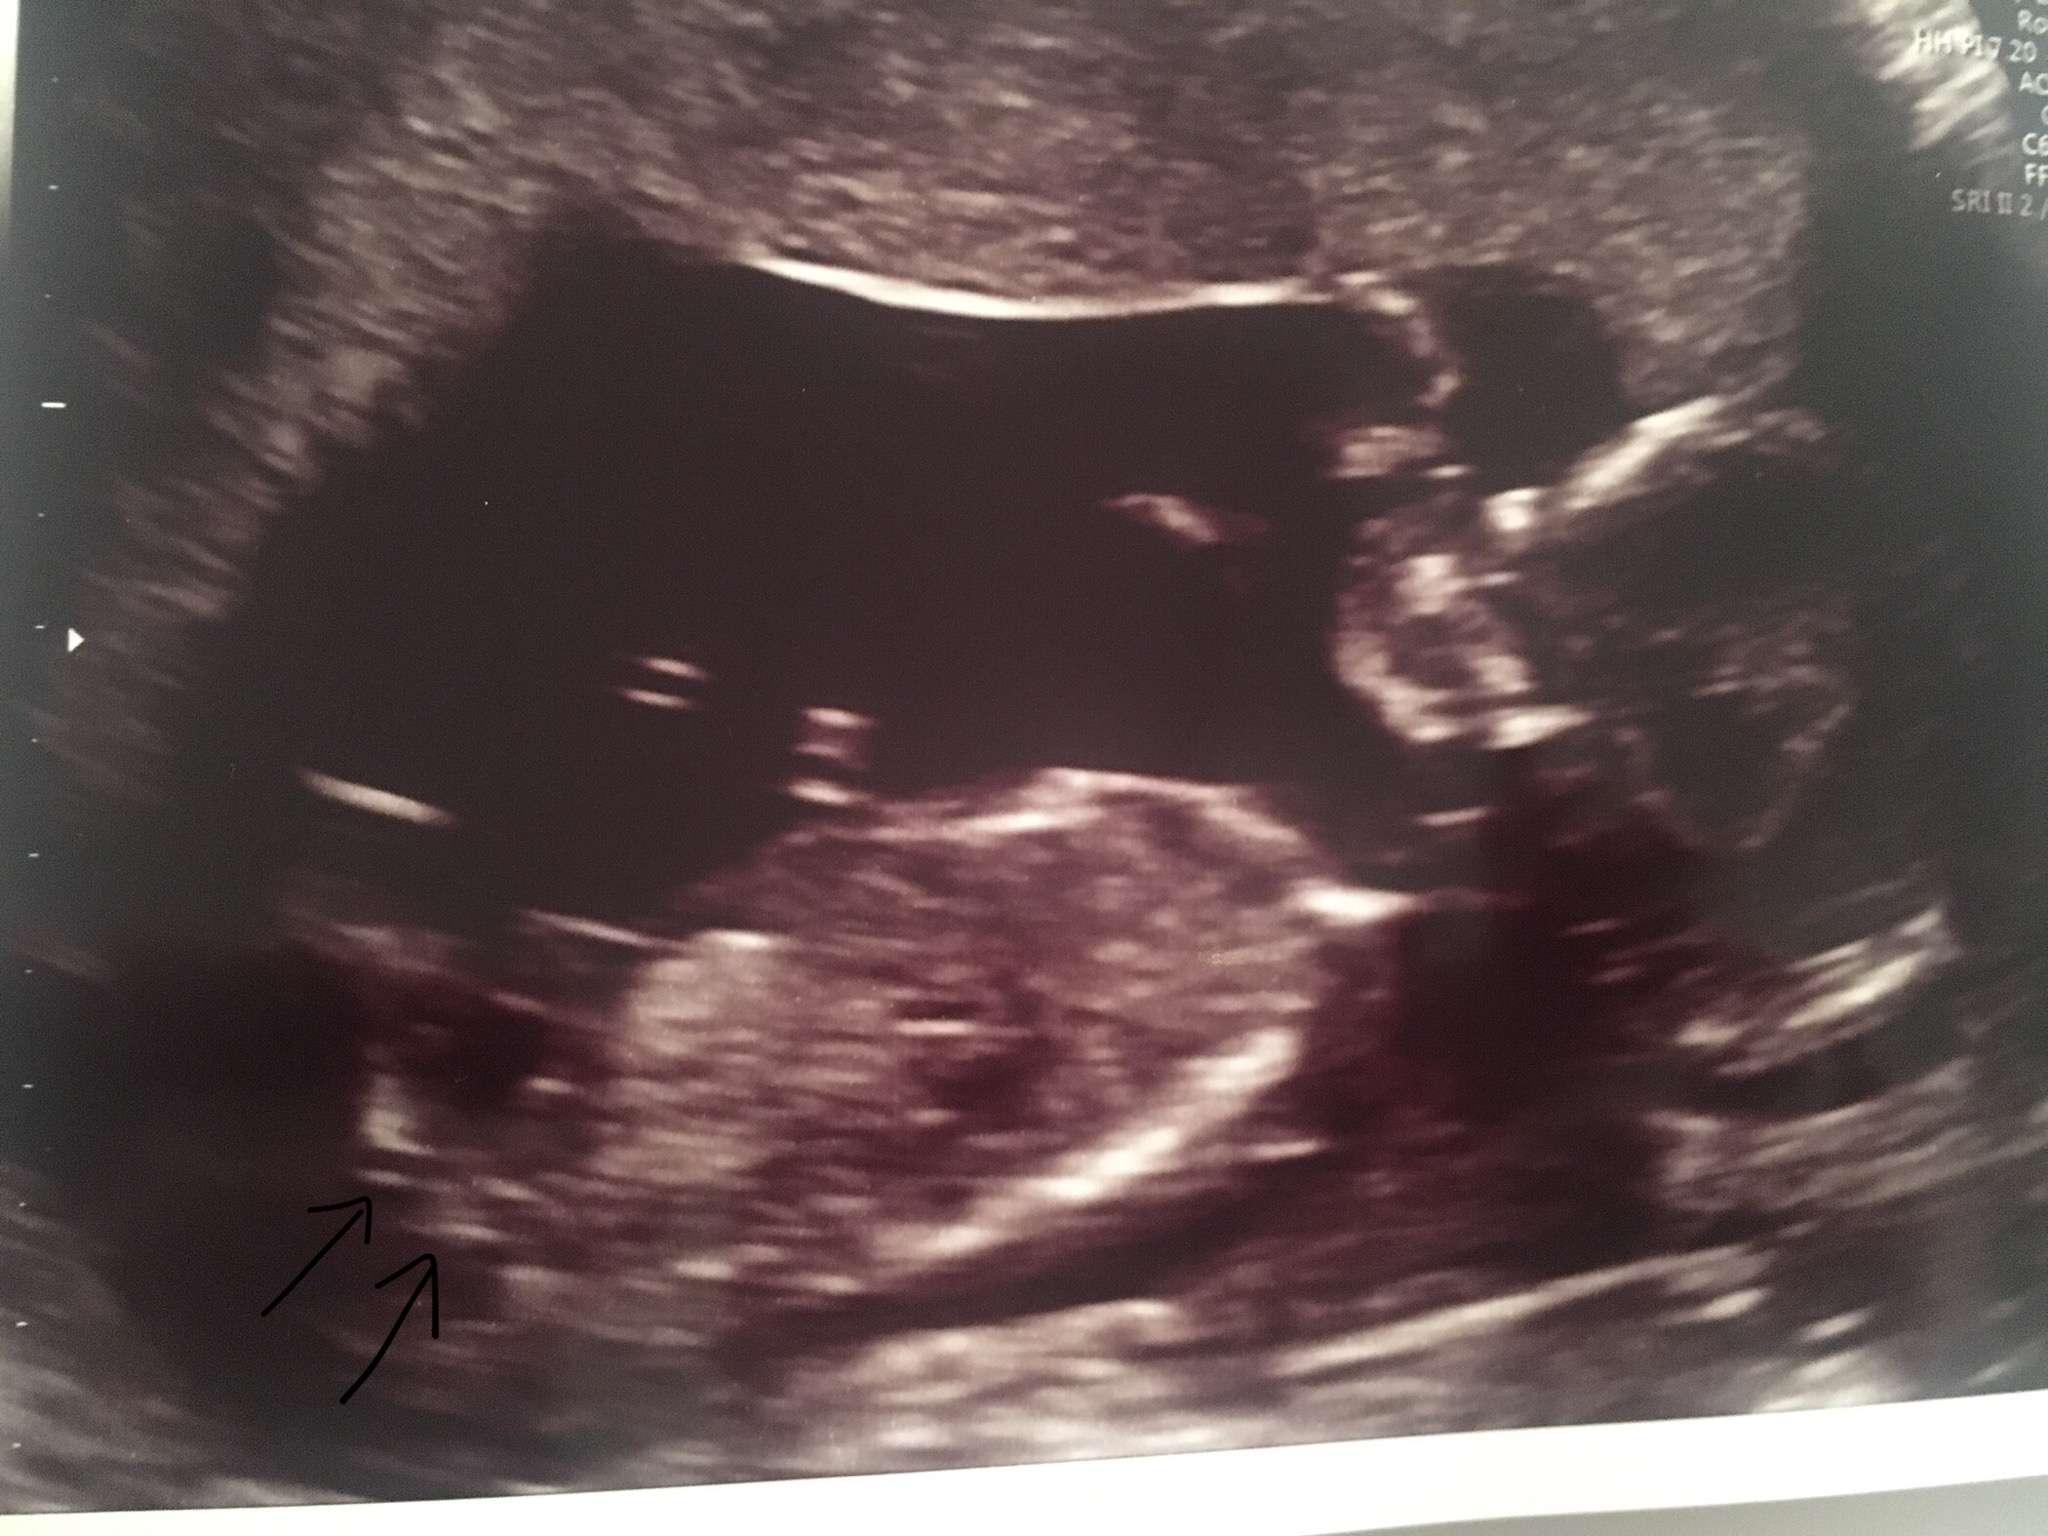

I am so impatient. My 12w dating scan did get a couple of girl guesses (no boy guesses) but it wasn’t terribly clear and my gender scan is booked for the 11th of Feb but I’m so impatient so I decided to have a scan today at 14+3 to have another look at the nub. I could clearlysee the nub at my dating scan it was a bright white line but today I couldn’t see anything. Would that make you think girl or would a penis become invisible at this stage too?

I will add the image to see if you can see the nub on the 14w scan.